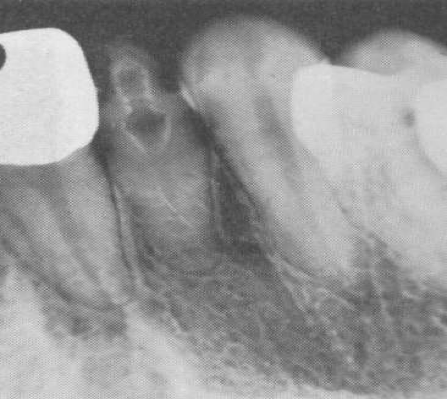

Dens in dente